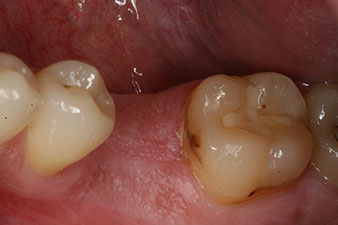

Un patient de 28 ans ayant des antécédents de tabagisme important a dû se faire extraire la dent 36 à la suite d’une parodontite apicale récidivante.

Vu que les dents voisines étaient globalement intactes, la seule solution pour remplacer la dent manquante était de poser un implant.

Cependant, six semaines après l’extraction on observe une ossification incomplète après la préparation du lambeau mucopériosté dans la région de l’ancienne alvéole mésiale.